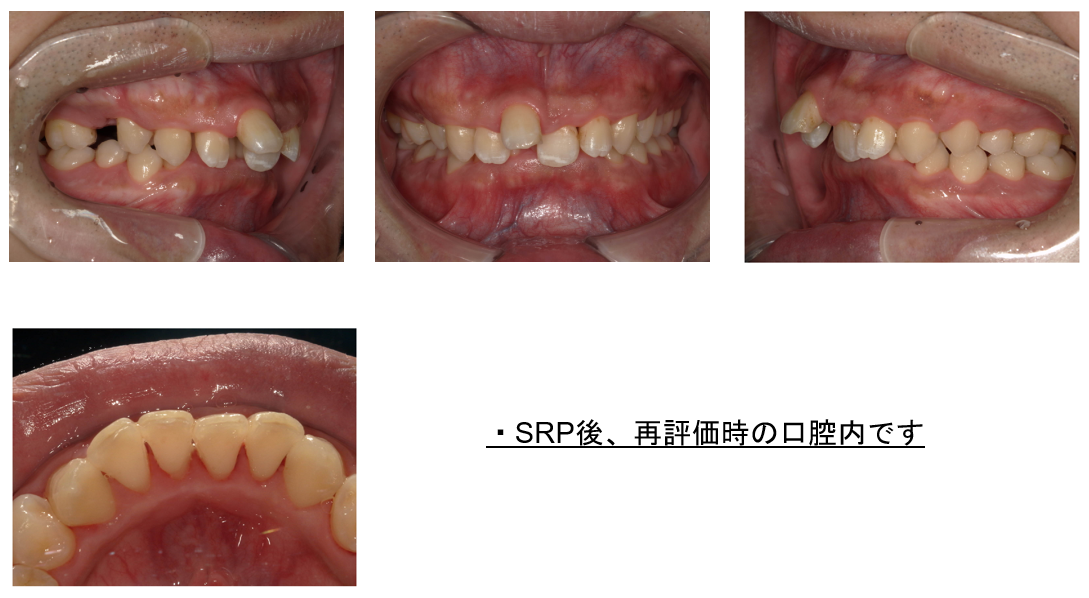

次に、炎症を起こしていた歯ぐきを鎮静化させるため、スケーリングから1週間程あけてから、歯ぐきの内部に沈着している歯石を除去する「SRP」を行います。

《専用の器具(超音波スケーラーや手用スケーラーなど)を使い、歯周ポケットの奥深くの歯石を物理的に除去します。また歯の根の表面を滑らかにする「ルートプレーニング」も同時に行い、プラーク(歯垢)が再び付着しにくいようにします。》

施術時は、痛みを感じにくいよう麻酔をしてから歯ぐき内部の歯石を丁寧に除去しています。